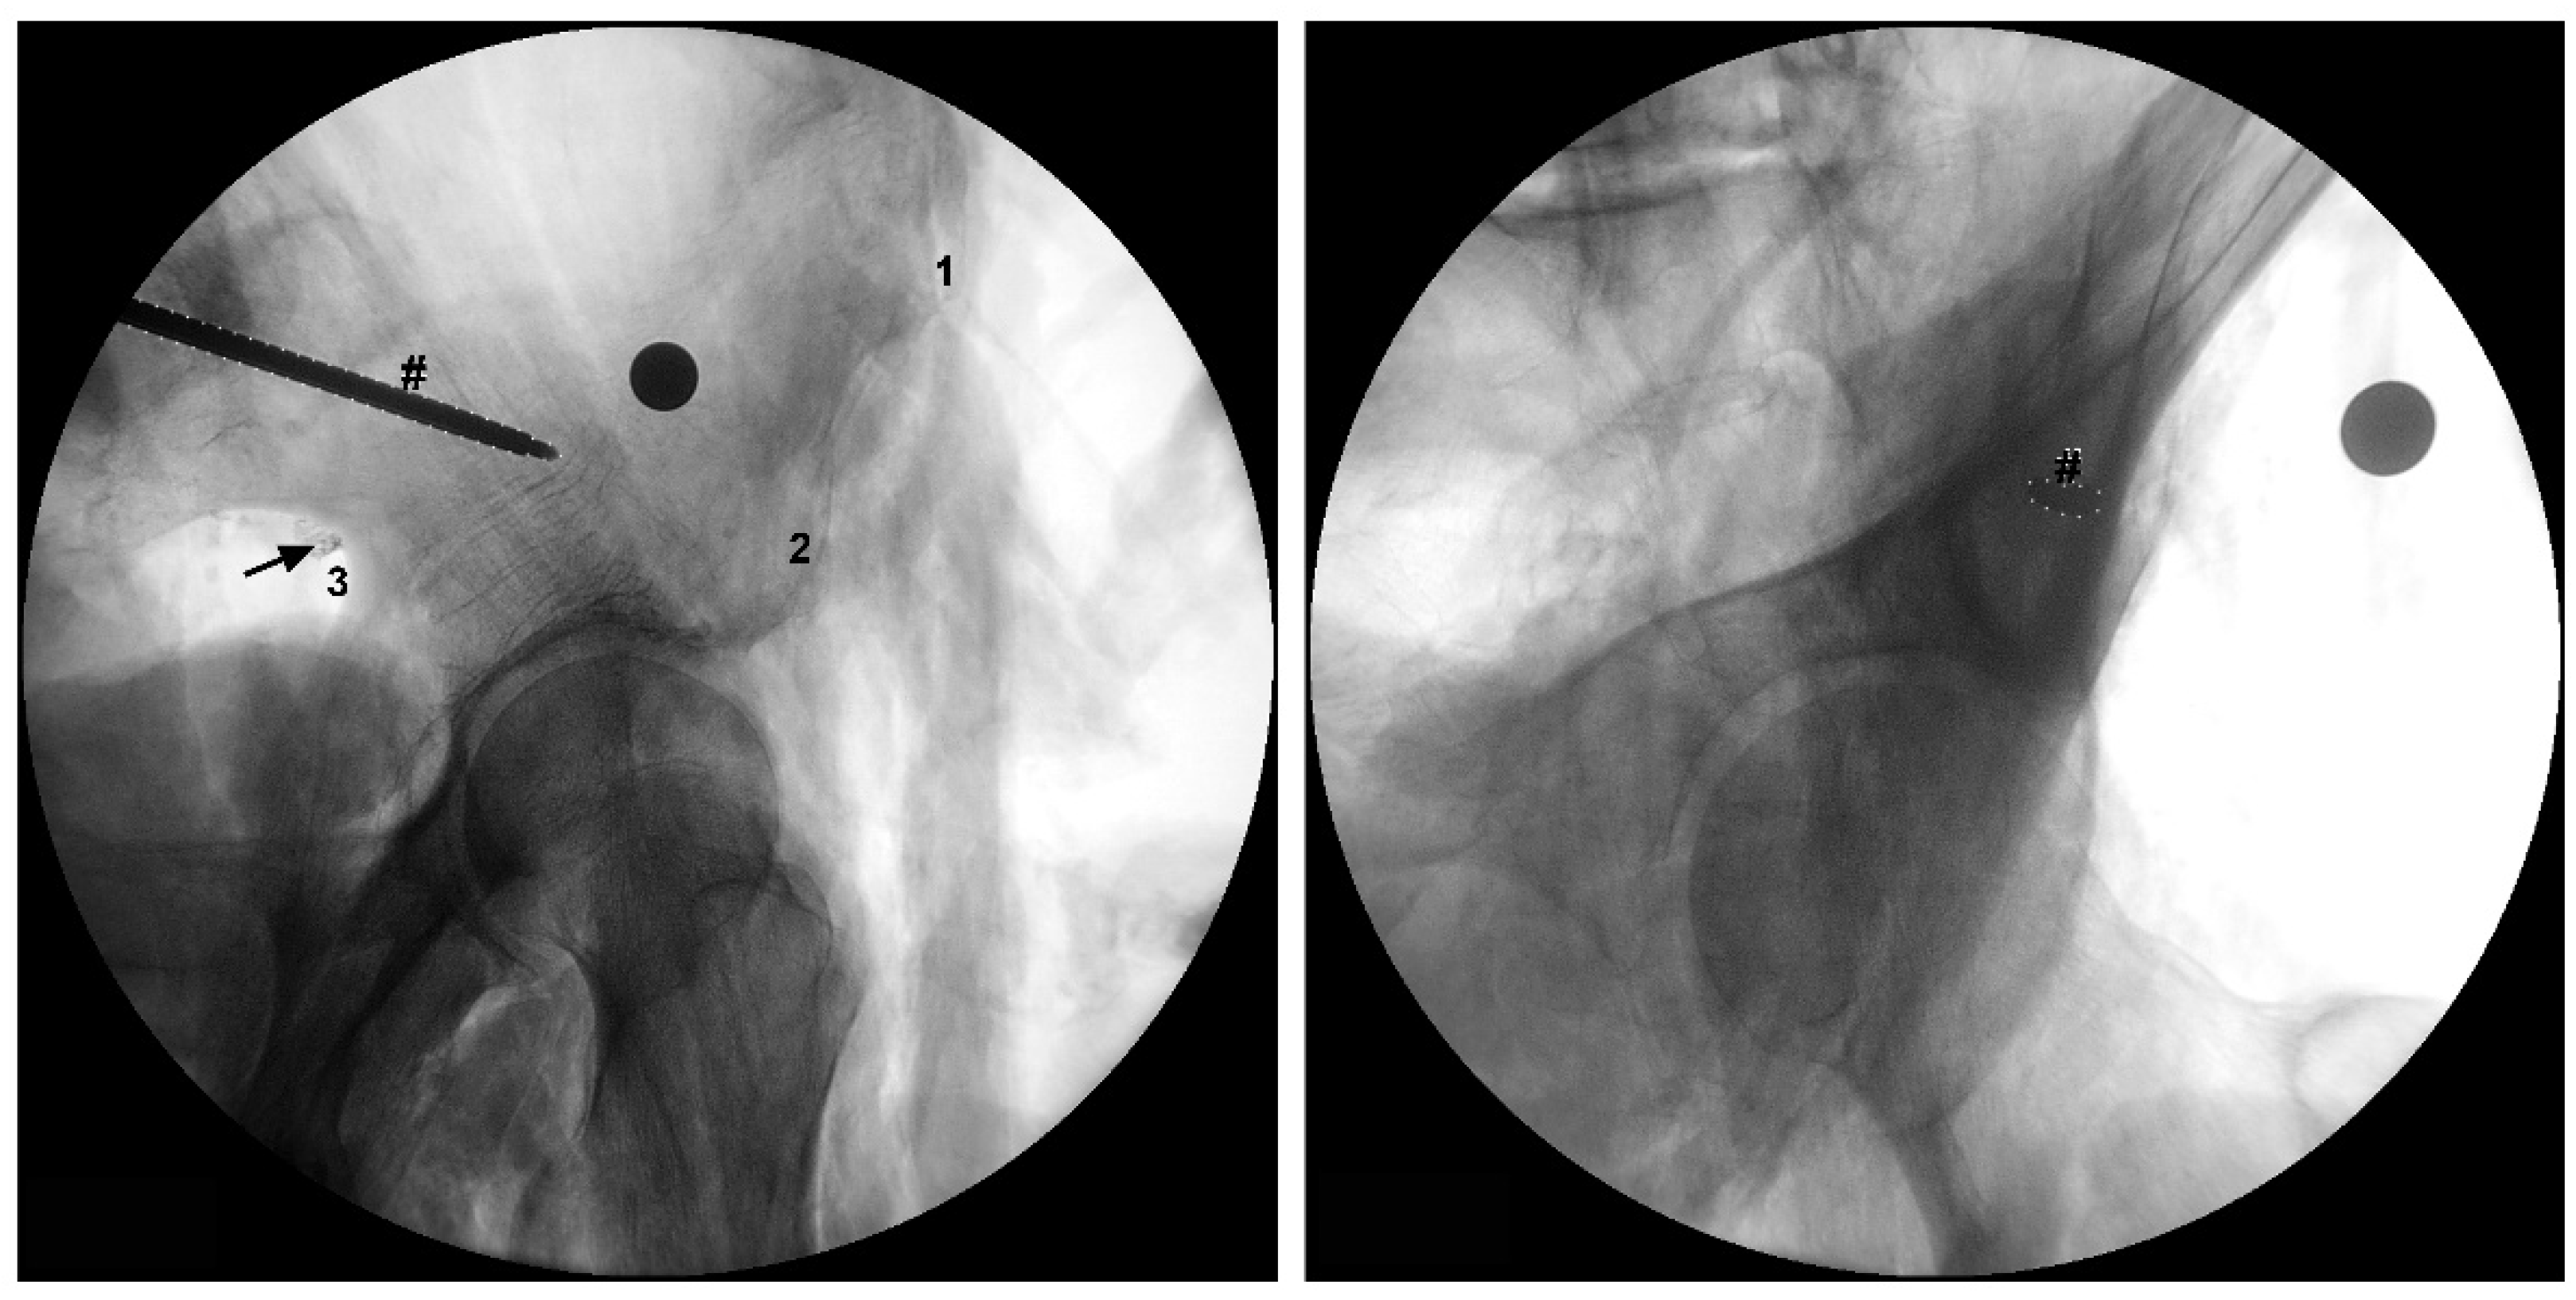

To take the measurements directly related to the SGN, firstly the superior gluteal neurovascular bundle was identified above the piriformis muscle and the SGN or its branches were carefully isolated at the greater sciatic foramen without moving it from its proper position (Figure 1). Then, we recorded the distances from the exit point of the SGN or its branches at the greater sciatic notch to the: 1) apex of the GT, 2) PSIS, 3) ASIS and 4) the inferior part of the IT. We also determined the exact exit point of the SGN or its branches in the greater sciatic notch (Figure 1). The emerging site of these nervous structures at the greater sciatic notch was recorded according to the following protocol: a) the distance values were considered positive if the nervous structures emerged superior to the greater sciatic notch apex; b) the distance values were considered negative if the nervous structures emerged inferior to the greater sciatic notch apex. We also determined the linear distance of each nervous structure to the bone at the greater sciatic notch. In one of the studied cadavers, we simulated the placement of an LC2 screw and we marked the SGN with a contrast medium at the point where it emerges from the pelvic cavity (Figure 3).

There are also reports of injury to the SGN during percutaneous iliosacral screw insertion. Collinge et al [11] performed a study in which the 58 sacroiliac screws were placed in the first sacral bodies, and observed lesion of the superior branch of the SGN and superior gluteal vessels in 10 of the 58 (18%) [11]. In our study, besides the GT, the SGN was also in close proximity to the PSIS, distancing 7.6 cm from it. The PSIS is an important surgical reference, due to its superficial location and usefulness in the localization of PIIS, making it a useful guide for percutaneous fixation of crescent ilium fractures (LC2 Screw). Therefore, we recommend caution when placing these screws, as a screw directed at the AIIS with a too inferior orientation can induce fracture of the upper limit of the greater sciatic notch and concomitant lesion of the SGN or its branches taking into account the close relation between these nervous structures and the greater sciatic notch (Figure 3).

Figure 3. Fluoroscopic images of a simulation of an LC2 screw placement. (a) An iliac oblique view. (b) An obturator outlet view. The symbol # indicates the trocar that simulates the LC2 screw. (a) The arrow indicates the superior gluteal nerve that was marked with a contrast medium at the point where it exits the pelvic cavity in direct contact with the greater sciatic notch. 1: anterior superior iliac spine (ASIS); 2: anterior inferior iliac spine (AIIS); 3: greater sciatic notch.